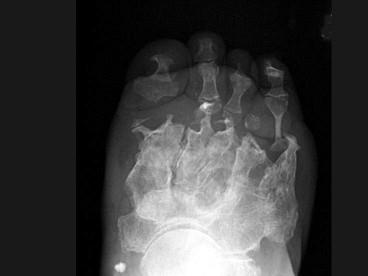

女,78岁,长期慢性手足畸形,无冷热、痛感,结合图像,最可能的诊断是?(?)A.骨麻风病B.骨梅毒C.骨结核D.痛风E.类风湿关节炎

问题 女,78岁,长期慢性手足畸形,无冷热、痛感,结合图像,最可能的诊断是?(?)

选项 A.骨麻风病 B.骨梅毒 C.骨结核 D.痛风 E.类风湿关节炎

答案 A